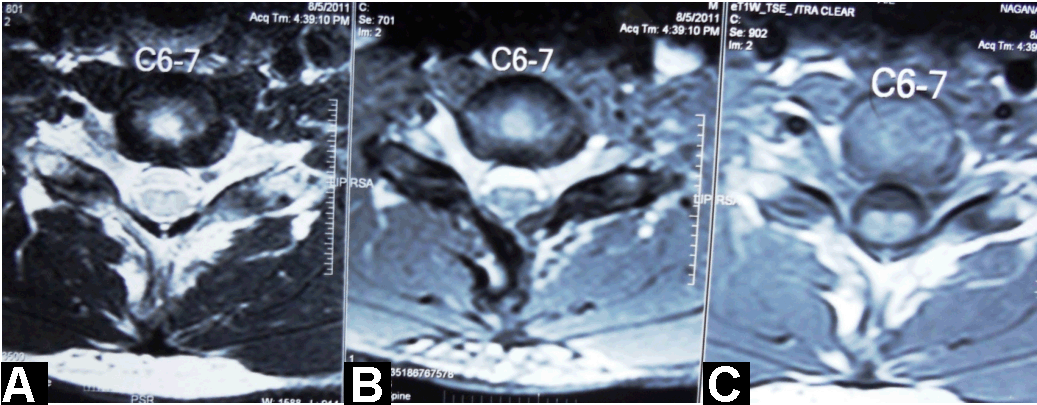

A 26-year-old male presented with progressive weakness and wasting in the distal muscles of both the upper limbs for last seven months. He noticed weakness while lifting dumbells, and later developed difficulty in handling small utensils and writing. He had no sensory symptoms. There was no preceding illness, trauma, exposure to toxins. His past medical history was noncontributory; he denied any allergic disease and none of his family members had similar symptoms. Neurological examination showed significant muscle loss of both upper limbs involving all muscle groups except for the deltoid and brachioradialis muscles. Strength was reduced in the finger extensors, abductor digit mini, flexor pollicis longus, abductor pollicis brevis, pronator teres and ulnar innervated muscles. Strength in lower limbs muscles was normal. Deep tendon reflexes were normal except slight hyporeflexia in triceps, the knee jerks were brisk bilaterally. Plantars were flexors. Mild action tremor was seen in fingers. Higher mental functions, gait, cranial nerves, cerebellar functions, and sensory examination were normal. There was no evidence of polyminimyoclonus or autonomic disturbances. The hematological investigations were normal. Cerebrospinal fluid showed glucose: 52 mg/dL, proteins: 13 mg/dL, and white cells: 4/mm3. Serum IgE was within normal limits. Electrophysiologic studies showed decreased amplitude in ulnar nerves with normal latencies and borderline low velocities; giant motor unit action potentials were seen in the muscles innervated by C7, C8 and T1 nerve roots, with fibrillations and positive waves. There was no evidence of conduction block. Plain cervical spine radiograph showed no abnormality and no misalignment of vertebral bodies. The magnetic resonance imaging (MRI) of the cervical spine in neutral position showed mild atrophy with mild loss of attachment between posterior dural sac and subjacent lamina of cervical cord at C6–C7 (Figure 1). On flexion view MRI cervical spine, there was anterior displacement of the dural sac and spinal cord with widening of posterior epidural space with engorgement of epidural veins (Figure 2). The axial sections showed anteroposterior flattening of the cord with intrinsic signal changes (Figure 3). Clinical, radiological and electrophysiologic findings in our patient were consistent with the diagnosis of bilateral symmetric Hirayama disease. The patient was advised to wear a soft cervical collar. On a three-month follow up the patient had shown no progression of his disease.

Figure 3: Axial sections shows Antero-posterior flattening of the cord with intrinsic signal changes.